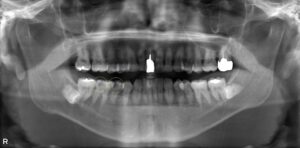

上顎洞炎を伴う根尖病変に対するマイクロスコープ下の根管治療

右上の痛みを訴えて来院されました。 CT撮影の結果、右上6番の根尖に黒い影があり、上顎洞内の粘膜も炎症で厚く腫れていることが確認できました… -